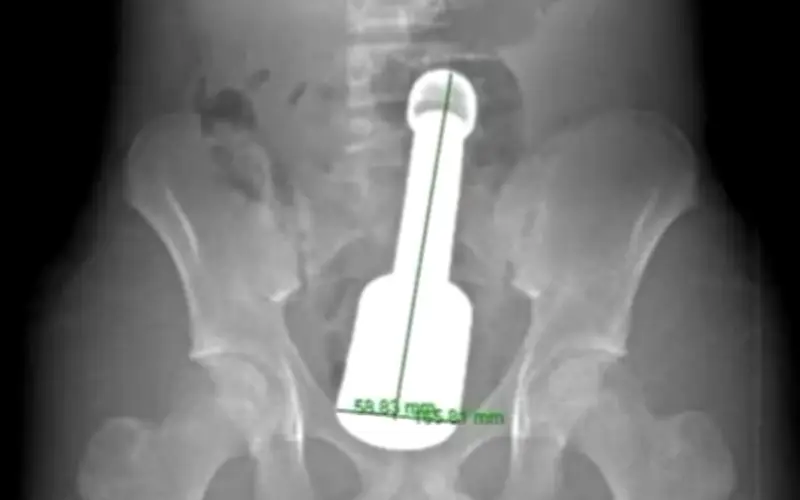

Bệnh nhân nhập viện trong tình trạng đau tức dữ dội vùng hạ vị, khiến các bác sĩ phải nhanh chóng tiến hành thăm khám. Kết quả chẩn đoán hình ảnh sau đó đã phát hiện một dị vật kim loại lớn mắc kẹt sâu trong trực tràng, gây chèn ép nghiêm trọng lên các cơ quan vùng chậu. Đây được xem là tình huống nguy hiểm, có nguy cơ cao dẫn đến các biến chứng nặng nề nếu không được xử trí kịp thời.

Ngay lập tức, một quy trình phối hợp liên khoa bao gồm Cấp cứu Ngoại, Chẩn đoán hình ảnh, Gây mê hồi sức và Ngoại tiêu hóa đã được kích hoạt để tìm ra phương án tối ưu nhất. Theo các bác sĩ, dị vật được xác định là một chiếc chày với chiều dài khoảng 18cm và đường kính 6cm.